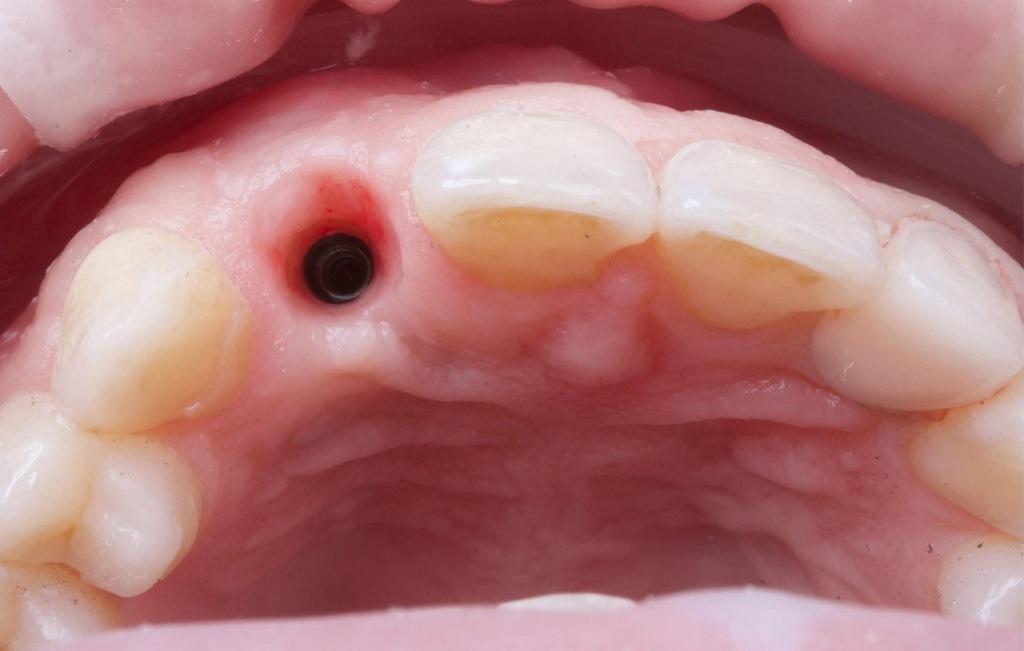

На первом приеме были получены цифровые снимки с помощью сканера Medit i700. Также были получены периапикальные рентгенограммы и стандартизированные интраоральные и экстраоральные фотографии. Для планирования лечения была создана виртуальная диагностическая карта. В день операции была проведена местная анестезия, и имплантат был атравматично удален с использованием техники эксплантации с обратным вращением. Место операции было обработано и очищено, и на лунку был нанесен коллаген I типа (фото 3).

Фото 3: Атравматичное удаление имплантата.